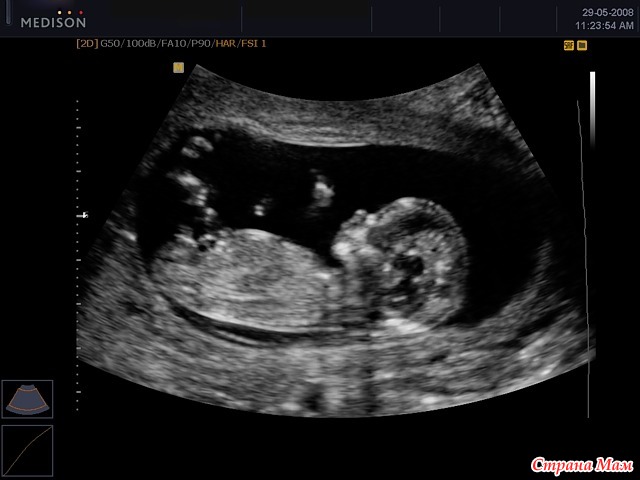

Только, что пришла с узи. Довольная, как слон

Я видела своего малыша, нам всего 12 неделек, а он уже такой большой

Я думала почти ничего видно не будет. Такое счастье осознавать, что в тебе живет жизнь

Будем ждать 20 неделек. Самое главное, все хорошо, прогрессирующая беременность

Немного смутило, что шейка матки, сказали длиннющая 39 мм. И в заключении низкая плацентация написали. Но я думаю, это не страшно т. к. узист сказал все хорошо